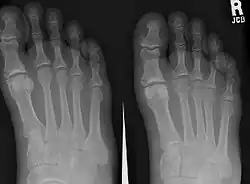

El quinto hueso metatarsiano es un hueso largo del pie, y es palpable a lo largo de los bordes externos distales de los pies. Es el segundo más pequeño de los cinco huesos metatarsianos. El quinto metatarsiano es análogo al quinto hueso metacarpiano de la mano[1]

Al igual que los otros cuatro huesos metatarsianos, puede dividirse en tres partes: base, cuerpo y cabeza.

La base es la parte más cercana al tobillo y la cabeza es la más cercana a los dedos del pie. La parte estrecha del centro se denomina cuerpo (o eje) del hueso. El hueso es algo plano, por lo que tiene dos superficies: la plantar (hacia la planta del pie) y la dorsal (la zona que mira hacia arriba al estar de pie).[1] Estas superficies son rugosas para la fijación de los ligamentos. El hueso está curvado longitudinalmente, de modo que es cóncavo por debajo y ligeramente convexo por encima.

La base se articula por detrás, mediante una superficie triangular cortada oblicuamente en sentido transversal, con el cuboides; y medialmente, con el cuarto metatarsiano. El quinto metatarsiano tiene una eminencia rugosa en la cara lateral de su base, conocida como tuberosidad o apófisis estiloide. La superficie plantar de la base está estriada para el tendón del músculo abductor del meñique.

La cabeza se articula con la quinta falange proximal, el primer hueso del quinto dedo.